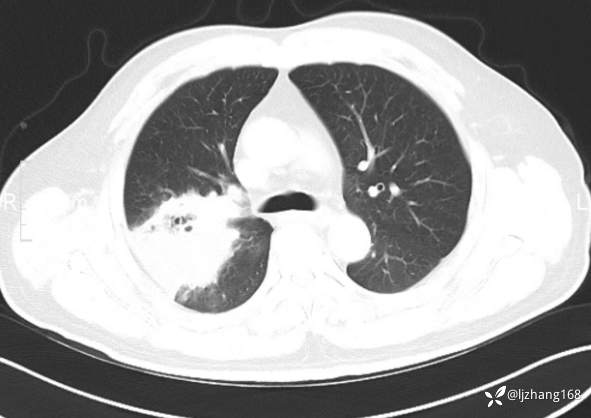

中年男患,右肺团片影,炎症0R肿瘤?

简要病史: 20+天前患者因受凉后出现阵发性咳嗽,咳少量白色粘痰,痰易咳出,伴活动后气短,伴纳差、乏力、全身酸痛,伴多汗,无痰中带血及咯血,无发热、畏寒及寒战,无潮热、盗汗,无夜间阵发性呼吸困难及端坐呼吸,无声嘶,无头晕、头痛,无黑矇、晕厥及意识障碍,无腹痛、呕血及黑便等不适,遂就诊于当地医院予以输液等治疗后未见明显好转(具体诊疗不详),现为进一步诊治就诊于我院门诊,以“右肺占位”收入我科。病来饮食欠佳,近期体重下降(具体不详)。既往糖尿病病史7+年,未规律监测血糖,血糖控制不佳。否认“高血压、冠心病及慢性肾脏病”等慢性疾病史。否认“肝炎、结核、伤寒”等传染病史。否认食物、药物过敏史。否认外伤、输血史,预防接种史不详。

辅助检查:糖化血红蛋白12.3%。肺炎支原体IgG、IgM、呼吸道合胞病毒均未见明显异常。胸部CT:右肺上叶阻塞性肺炎。